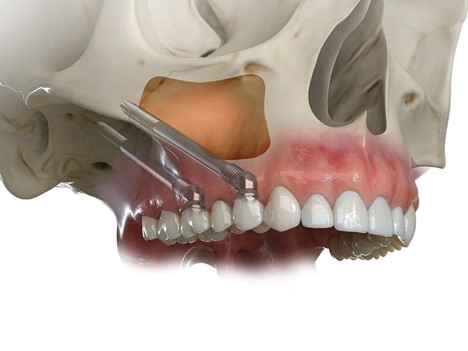

Zygoma Implant – kỹ thuật cấy ghép implant vào xương gò má (zygomatic bone), được phát triển bởi Giáo sư – Tiến sĩ Per-Ingvar Brånemark, chính là giải pháp đột phá cho những trường hợp này.

Zygoma Implant là loại implant dài hơn implant thông thường (30 – 55 mm), được đặt vào vùng thân xương gò má – vùng xương cứng, dày và ít tiêu theo thời gian.

- Tránh các phẫu thuật nâng xoang, ghép xương khối phức tạp

- Giảm sang chấn, giảm nguy cơ viêm nhiễm và biến chứng

3. Phẫu thuật cấy ghép

- Thực hiện bởi bác sĩ Implant chuyên sâu

- Gây tê tại chỗ hoặc gây mê/tiền mê (tùy trường hợp)

- Implant được đặt chính xác theo kế hoạch kỹ thuật số